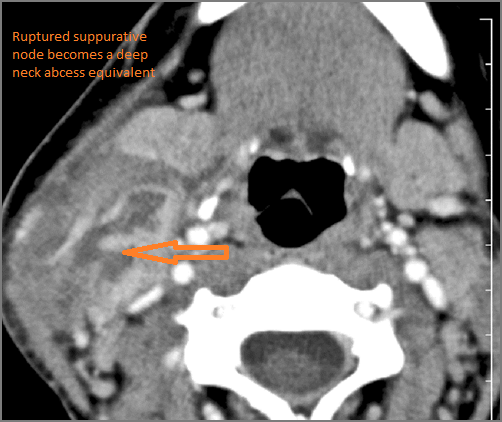

There is edema/abscess within the adjacent deep neck, and/or retropharyngeal space. |

Yes | NA |

If there is suppurative cervical adenopathy the purulent material outside the lymph node(s) capsule(s). |

No | NA |